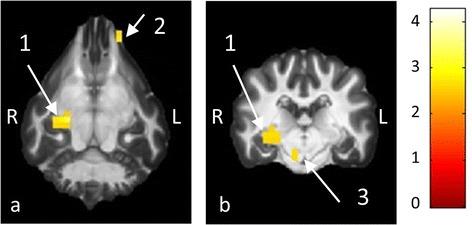

With the group analysis, significant activations matching the position of the right superior olivary nucleus, lateral lemniscus and internal capsule were identified, which could not be detected in the single animal analysis. In addition, a large cluster of activated voxels in the auditory cortex was found. The contrast of the RIS condition (including pitch) with Gaussian noise (no pitch) showed a significant effect in a region matching the location of the left medial geniculate nucleus.

通过组分析,确定了与右侧上橄榄核、外侧丘系和内囊位置相匹配的显著激活,而在单只动物分析中未检测到这些激活。此外,在听觉皮层发现了一大群激活的体素。RIS条件(包括音高)与高斯噪声(无音高)的对比在与左侧内侧膝状体位置匹配的区域显示出显著效应。